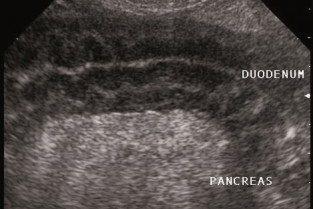

Le pancréas : un organe complexe et souvent mal connu. A partir de cette journée qui lui est totalement dédiée, nous allons explorer à la fois sa partie endocrine et exocrine, pour qu'il ne présente plus de secrets pour vous. Le diabète, quel que soit son type, ainsi que les pancréatites et autre insulinome ne seront plus jamais un casse-tête inextricable après cette mise au point.

- décrire les examens d'imagerie permettant de dépister des anomalies du pancréas ;